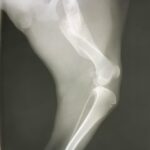

Sweet lovely Maisey is just under a year old. She was hit by a car and suffered a fractured femur. Unfortunately, she either didn’t have owners, or if she did, they didn’t bother to take her to a veterinarian to be treated. So Maisey’s body healed all on it’s own, leaving her right femur shorter than her left.

Maisey is fully grown and weighs just under 25 lbs. She has a soft, slightly shaggy mid-length coat, and is not a heavy shedder. She gets around fine on her healed leg. Aside from a slight hitch in her gait she runs and plays as though she was never injured. Maisey is spayed, fully vaccinated and in great health.